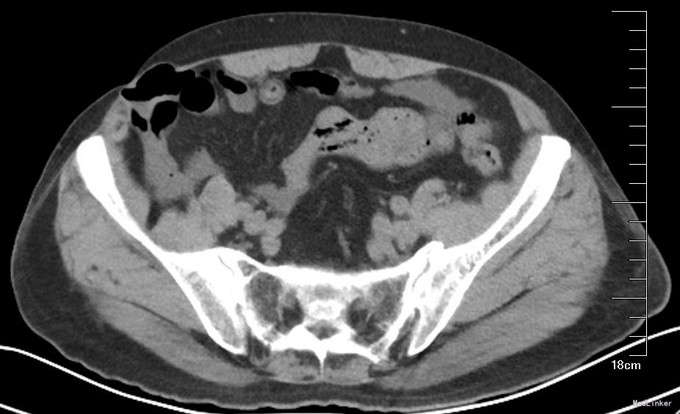

查体:腹平软,肠音正常,全腹无压痛及反跳痛,无肌紧张,右下腹见一斜形切口痕,未见明确包块突出,切口下方空虚,无压痛,站立及增加腹压时似有包块突出。左侧腹股沟区未见异常。辅助检查:腹部CT(图1):右下腹壁切口疝.

讨论:腹腔镜切口疝手术最需要跟患者交待清楚同时术中最需要注意的就是肠管破损。切口疝原因一般是开腹手术术后切口感染,腹壁缺损。腹腔脏器尤其是肠管跟腹壁可能广泛粘连。肠管破损原因:1.建立气腹时扎漏。2.分离粘连时破损。3.分离时肠管浆膜破损,周围血运障碍,可能术后肠瘘。如何避免:1.远离疝区域建立气腹,或者直接直视下开放性气腹。2.分离时尽量远离肠管,使用超声刀分离,减少电设备电刀等热损伤。腹腔镜分离时更容易出现肠瘘,不是因为腹腔镜肠瘘的机会增加,而是在术中肠瘘发生时没有及时发现处理。可能腹腔镜视野未及时探到,腔镜下缝合技术较开腹难度大,较少采用预防性缝合防止术后肠瘘。肠瘘发生后处理:及时早期手术。冲洗腹腔,减少感染,缝合瘘口或切除肠管。一般在腹腔感染状态下,主张取出补片,感染一般会造成补片修补失败。该患者术前CT可见切口疝疝囊为皮肤,皮下肌肉缺损,小肠肠管直接与皮肤相接,分离肠管时造成肠瘘风险增加。